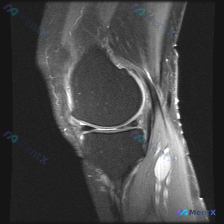

今天看到一个很有代表性的读片病例,提问说要找半月板的潜在异常,整理出来分享一下思路,很容易踩思维的坑! 病例基本信息 这是一份单张膝关节MRI-T2序列矢状位图像,图像质量良好,解剖结构清晰,无明显运动伪影。 影像读片结果 按标准放射学流程读片: 1. 半月板: 本层面观察到的半月板呈典型三角形低信...